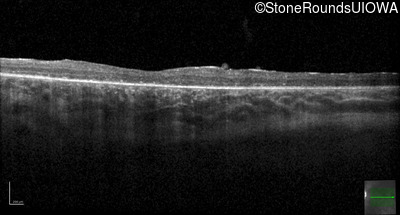

Optical Coherence Tomography - Left - 20/50

Exemplar / OCT Stack

OCT Stack